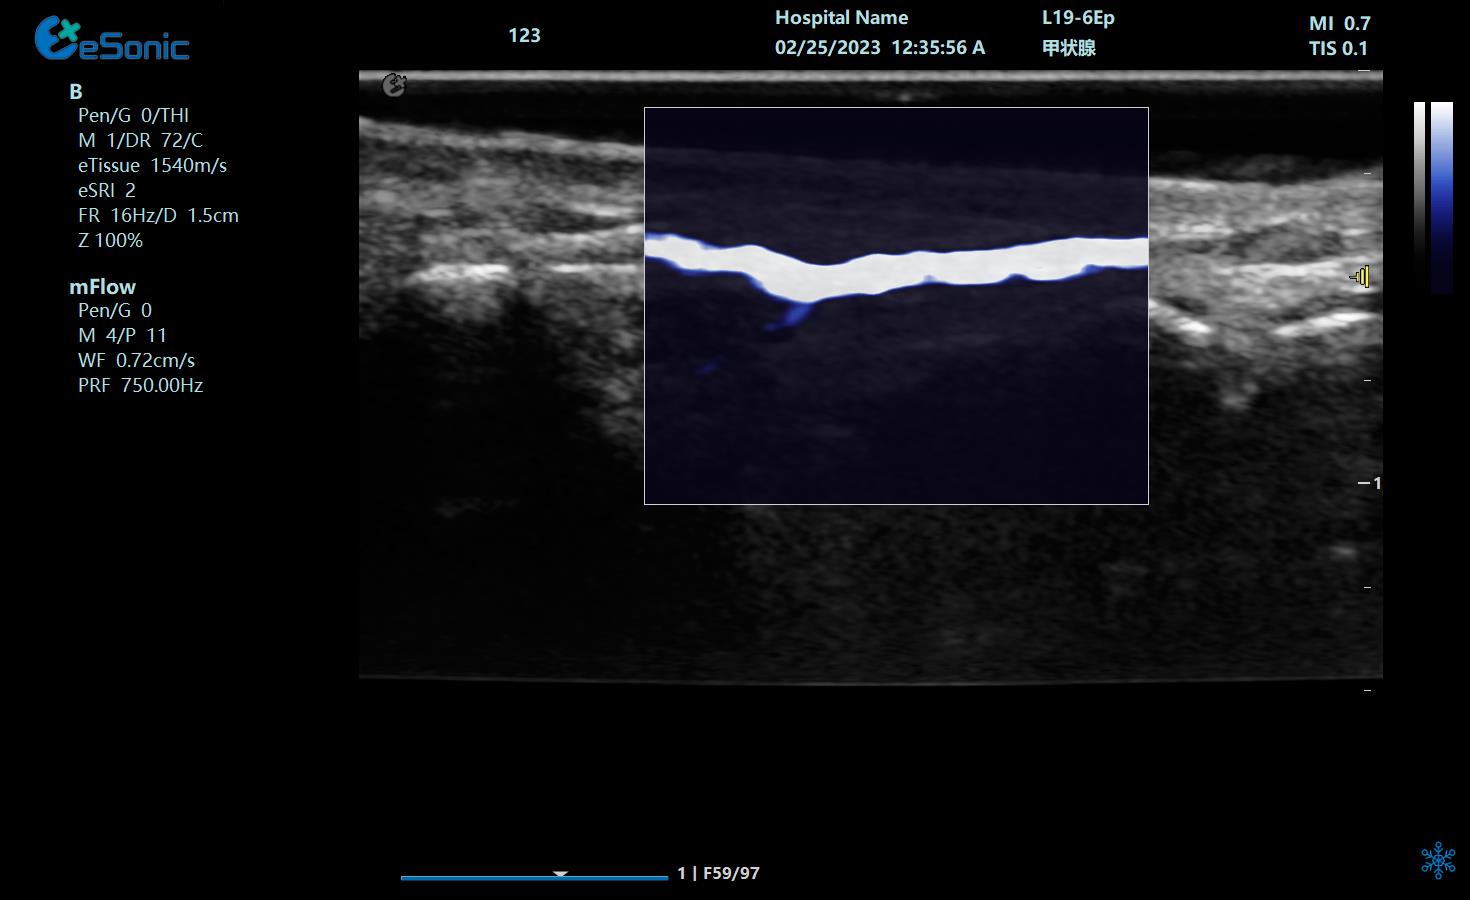

膈肌厚度检查

image.png

探头:高频线阵探头

部位:放置于腋前线与腋中线,7/8肋间或8/9肋间,沿肋间隙放置,观察和测量膈肌的厚度。

功能:M型超声,膈肌测量包

膈肌厚度变化

膈肌厚度测量

呼气末膈肌厚度正常值为2.0-3.5cm